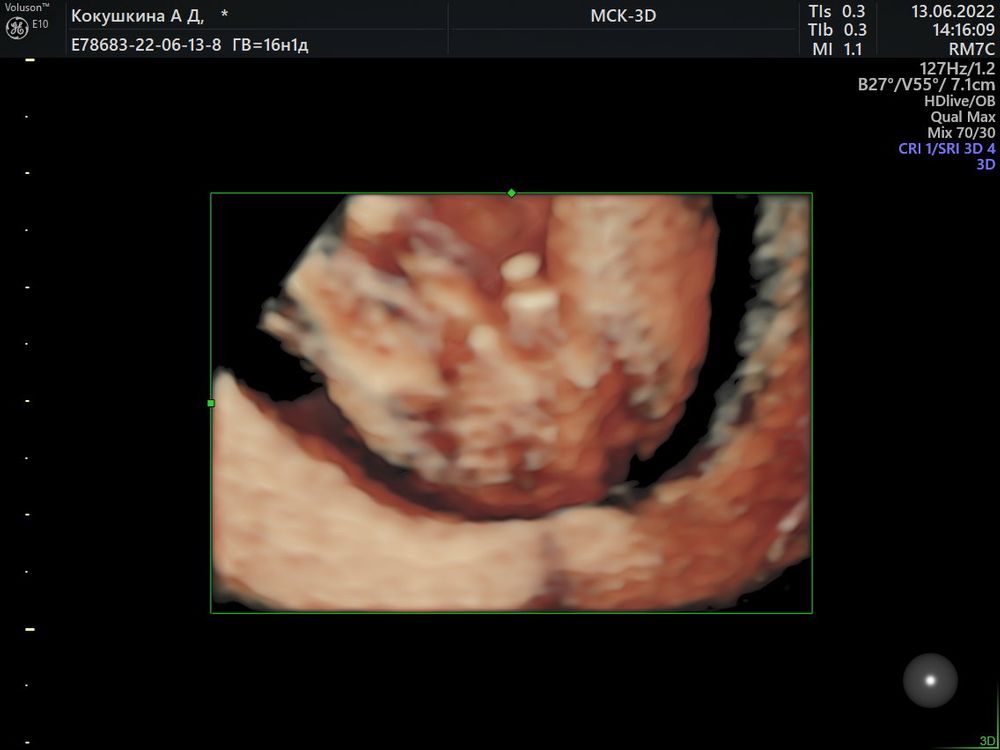

Определение пола 16 недель 🙏🏻

Девочки , подскажите пожалуйста кто вам кажется на фото. 🙏🏻16 недель 💫

Ирина, в 16 недель не половой бугорок, а уже хорошо развитые половые органы